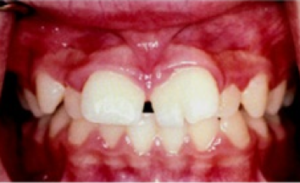

- Gigi Berlebih (Supernumerary Teeth)

Supernumerary teeth adalah gigi yang berkembang melebihi jumlah normal, dan gigi yang berkembang tersebut dapat normal secara morfologis, atau abnormal. Supernumerary teeth yang terletak diantara dua gigi depan atas disebut mesiodens. Faktor penyebabnya berasal dari herediter atau keturunan.

Jika anak mengalami hal ini, maka orangtua tidak perlu kuatir. Periksakan anak ke dokter gigi, biasanya dokter kana melakukan rontgen panoramik terlebih dahulu untuk memastikan gigi berlebih dan benih gigi tetap lainnya. Tindakan selanjutnya biasanya adalah mencabut gigi berlebih.